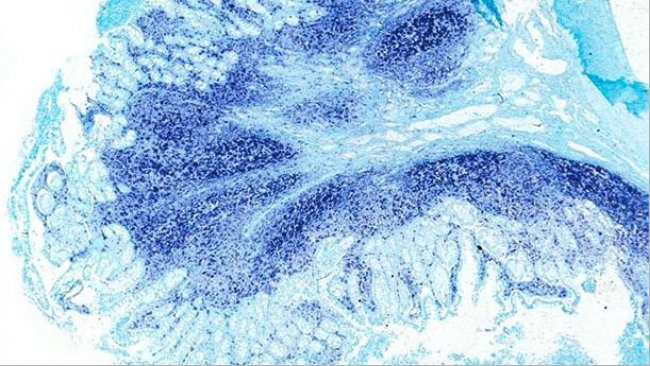

Seit kurzem geht man davon aus, dass PCV2 ein Krankheitserreger ist, der bei Schweinen Diarrhö auslöst, und es wurde vorgeschlagen, die PCV2-Darmerkrankung (PCV2-ED) als eigenes Krankheitsbild innerhalb der Erkrankungen, die durch porcine Circoviren induziert werden (PCVDs), zu betrachten.